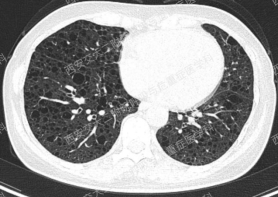

上图所示肺部多发囊性病变,双肺广泛分布,直径在2-10mm之间,壁薄,囊壁间组织相对正常。结合育龄期女性等临床资料,不难诊断淋巴管平滑肌瘤病(LAM)。对疑似LAM的女性的初步评估还应包括血管平滑肌脂肪瘤的筛查、淋巴管受累以及是否存在未被诊断的结节性硬化症。该例患者经评估后诊断散发型S-LAM。

该患者肺功能下降达到治疗标准,但患者及家属暂不考虑用药,选择观察,目前随访中。曾咨询乘飞机到拉萨的问题,鉴于症状稳定,可乘坐飞机,但不建议上高原。